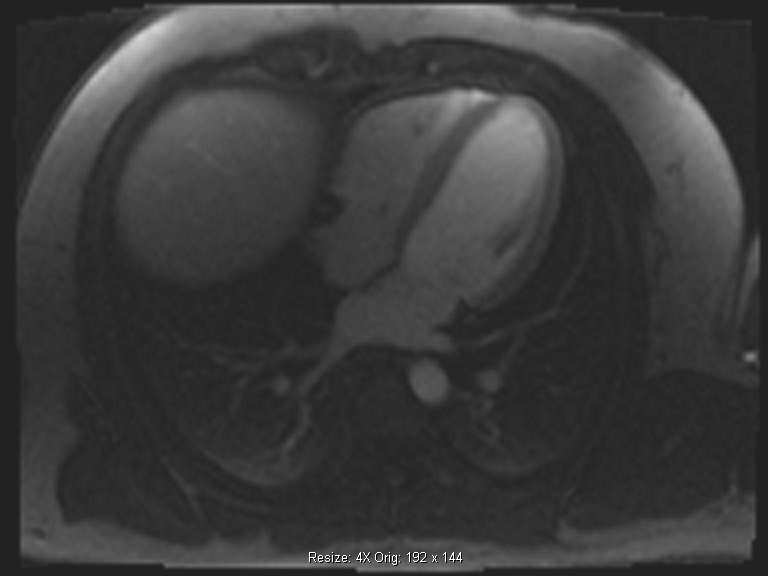

Η κλασική μαγνητική τομογραφία καρδιάς είναι μία από τις πλέον σημαντικές απεικονιστικές τεχνικές για τη διάγνωση των καρδιαγγειακών παθήσεων. Είvαι μια εξέταση φιλική, δεν απαιτεί καμία ειδική προετοιμασία από τον ασθενή και προσφέρει τη δυvατότητα λήψης τoμoγραφικώv εικόvωv άριστης ποιότητας. Τα τελευταία χρόνια οι διαγνωστικοί ορίζοντες της απεικόνισης της καρδιάς έχουν διευρυνθεί με κάποιες νεότερες τεχνικές, εκ των οποίων οι πλέον καινοτόμες εφαρμόζονται στο Metropolitan Hospital.

Μαγνητική τομογραφία καρδιάς

To Τμήμα Μαγνητικής Τομογραφίας Καρδιάς του Μetropolitan Hospital διαθέτει σύγχρονους μαγνητικούς τομογράφους 1.5 & 3 Τesla και εξειδικευμένο προσωπικό με πιστοποίηση SCMR level 3 και EACVI level 3 για τη διενέργεια εξετάσεων μαγνητικής τομογραφίας καρδιάς.